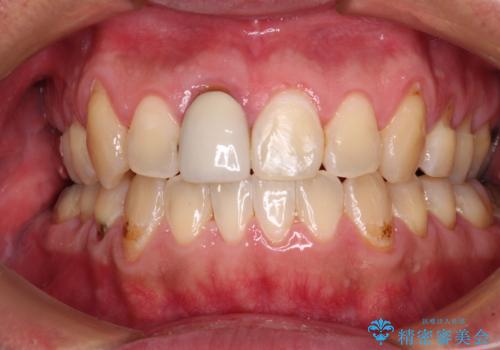

- 前歯のデコボコを改善したいと来院された患者様です。

口元の突出感はないものの、上顎前歯のデコボコが著しかったため、上下顎左右小臼歯4本を抜歯することとしました。

上下の正中位置を改善するため、右下は第一小臼歯を、その他は第二小臼歯を抜歯することとしました。

第二小臼歯抜歯の矯正治療は、治療期間が長引くことが多いですが、動きが非常に良く、予定の治療期間で終えることができました。

上下の正中も思っていた以上に良い位置に改善されました。